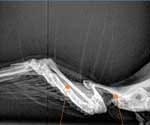

Images 48 and 49: 6- year-old male budgerigar with a Sertoli-cell tumor (tumor of the ovaries or testes). Note the soft tissue mass in the mid-coelom (main body cavity) and polyostotic hyperostosis (enlargement and thickening of the long bones). Red arrows point to long bones; black arrow to soft tissue mass (image courtesy H. Bowles) 7